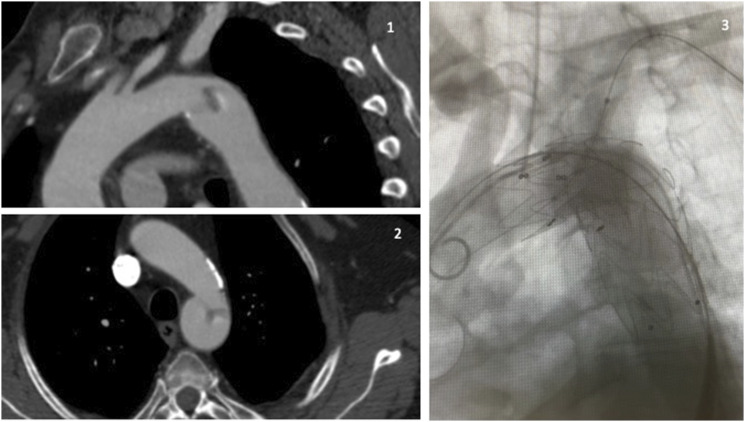

ObjectivesWe present two clinical cases of association between symptomatic free-floating thrombus (FFT) in thoracic aorta and rheumatoid arthritis (RA).MethodsIn the first patient, we observed a recent onset of peripheral and visceral signs of embolization: after a first treatment with anticoagulation, our Aortic team scheduled the coverage of FFT (sited in zone 1 of the aortic arch) with an anatomical debranching of anonymous trunk and left carotid artery, a left carotid-subclavian bypass, and a TEVAR of the aortic arch with proximal landing in zone 0 of the arch. The second case was characterized by chest pain, left upper limb ischemia, and CTA evidence of an FFT in zone 3 of the aortic arch; we planned a chimney-TEVAR on the left subclavian artery and descending thoracic aorta (with proximal landing in zone 2 of the aortic arch) to exclude the FFT.ResultsNo complications resulted and no new embolic episodes were registered.ConclusionsEvaluating the aorta is warranted in all patients with peripheral emboli of uncertain pathogenesis. In our opinion, the endovascular treatment of a symptomatic FFT could represent an effective and safe solution in a patient fit for endovascular surgery, but larger studies are required to define a personalized treatment strategy.